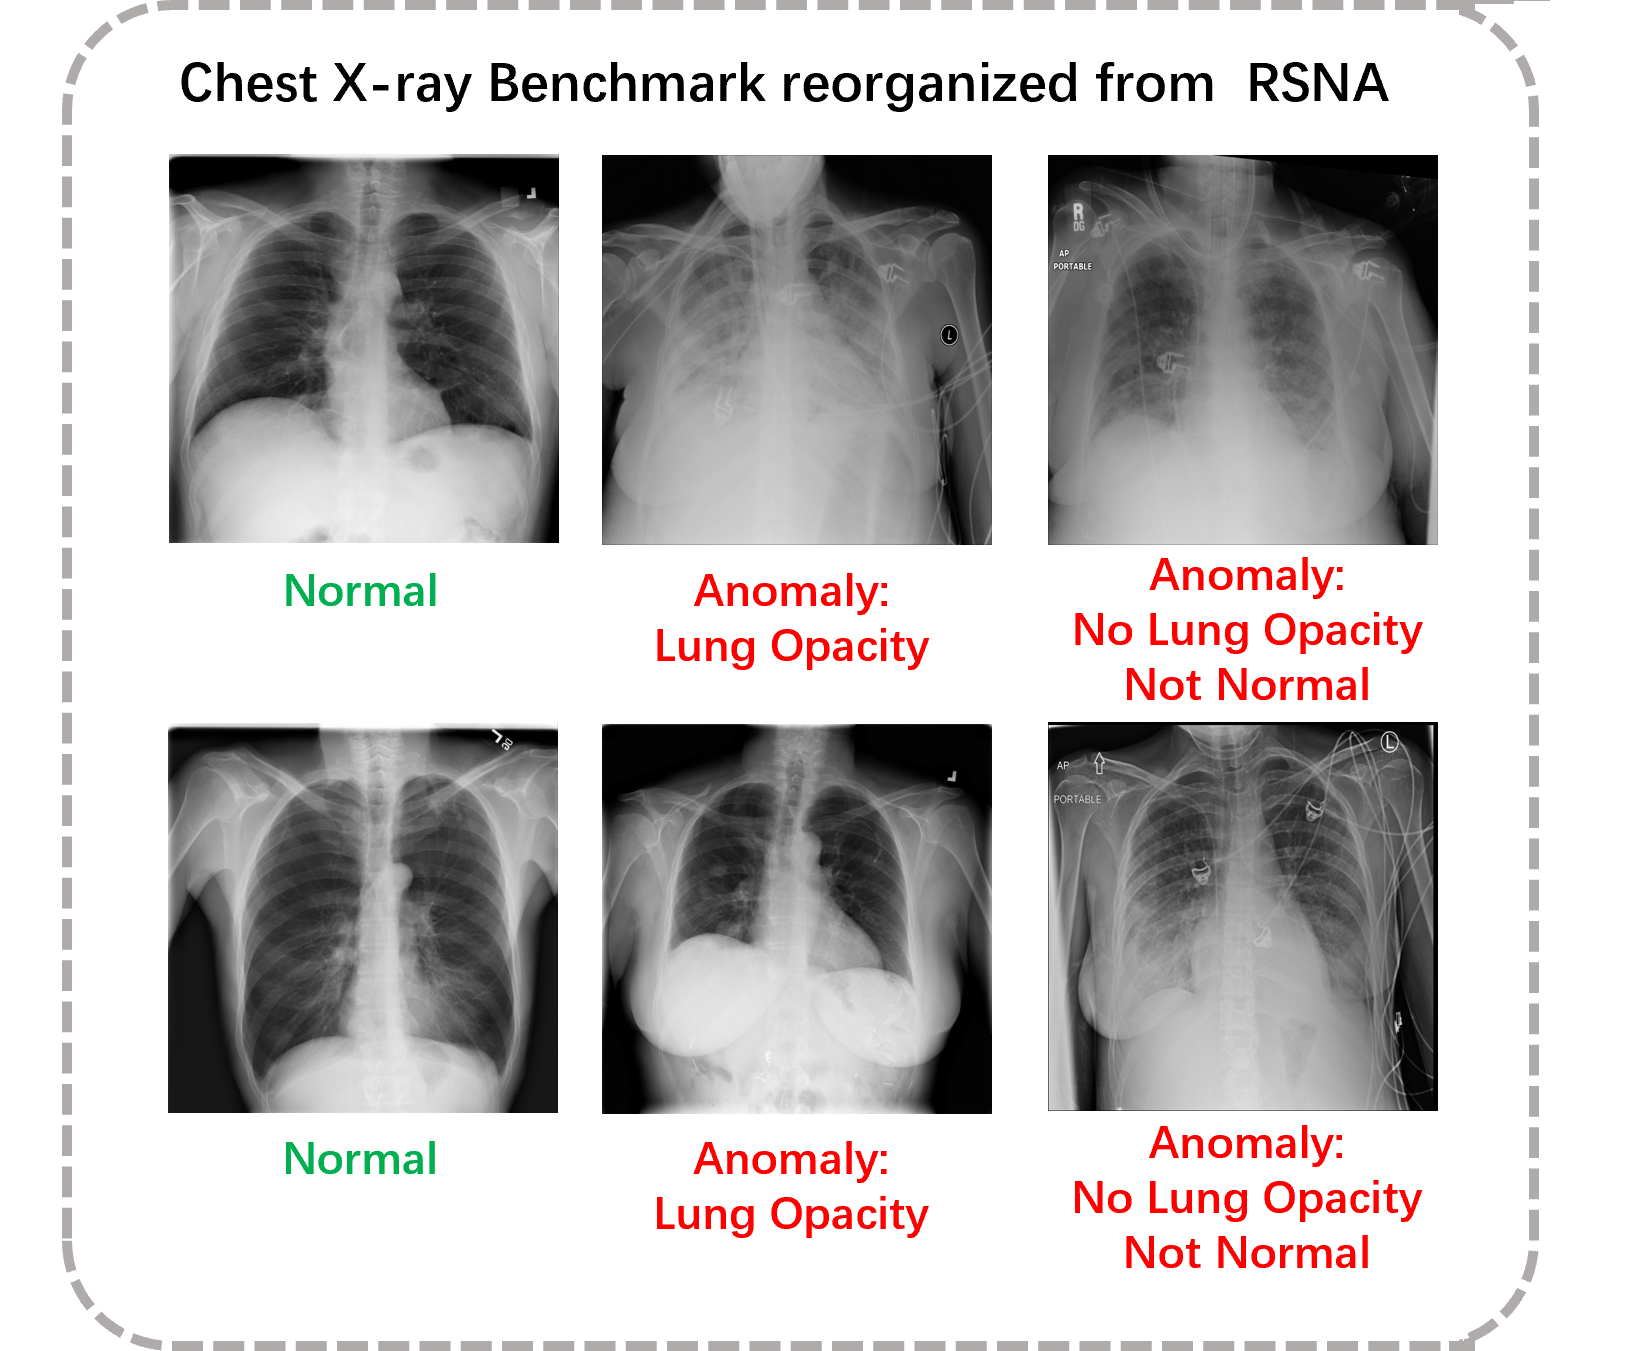

RSNA [63], short for RSNA Pneumonia Detection Challenge, is originally provided for a lung pneumonia detection task. The 26,684 lung images are associated with three labels: "Normal" indicates a normal lung condition, "Lung Opacity" indicates the presence of pneumonia, "No Lung Opacity/Not Normal" represents a third category where some images are determined to not have pneumonia, but there may still be some other type of abnormality present in the image. All images in RSNA are in DICOM format.

We utilized the provided image labels for data re-partition. Specifically, "Lung Opacity" and "No Lung Opacity/Not Normal" were classified as abnormal data. The reorganized AD dataset including 8000 normal images as training data, 1490 images with 1:1 normal-versus-abnormal ratio in the validate set, and 17194 images in the test set. Examples of the chest X-ray dataset are provided in Fig. 8.

Figure 8: Our proposed chest X-ray benchmark consists two types of anomalies. These anomalies are clearly labeled in the images, and all of them are considered as anomaly samples.